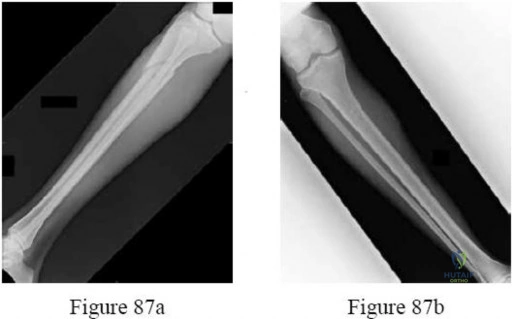

Question 39:

Correct Answer: Floating knee; fat embolism syndrome

Explanation:

An ipsilateral fracture of both the femur and tibia is termed a 'floating knee'. This high-energy injury pattern reflects massive trauma and is associated with a significantly higher risk of systemic complications, particularly fat embolism syndrome and acute respiratory distress syndrome (ARDS), compared to isolated long bone fractures.